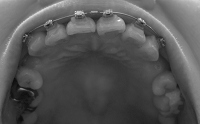

そんなわけで、ここんとこ変化がなくて寂しいので、この7ヶ月の変化が分かるように写真を並べて自分を励ますことにします~

ねね、全然違いますよね!!

正面から見たところなんて、こうやって見ると別人ですよね。